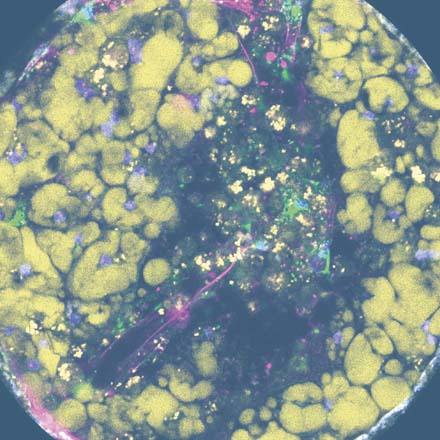

PhysioMimix organ-on-a-chip models are comprised of human cells and tissues whose phenotypes and functions reliably mimic those in vivo. By recreating human physiology in the lab, these models can be used for a myriad of applications that further our understanding of disease mechanisms, uncover potential therapeutic targets, and assist with the safe and efficacious development of potential therapeutics.

Studying disease models provides insight into disease cause and progression. They help to identify potential therapeutic approaches and are used to assess drug efficacy. Our models functionally mimic the organ and give a realistic expression of the disease phenotype to ensure more clinically translatable data.